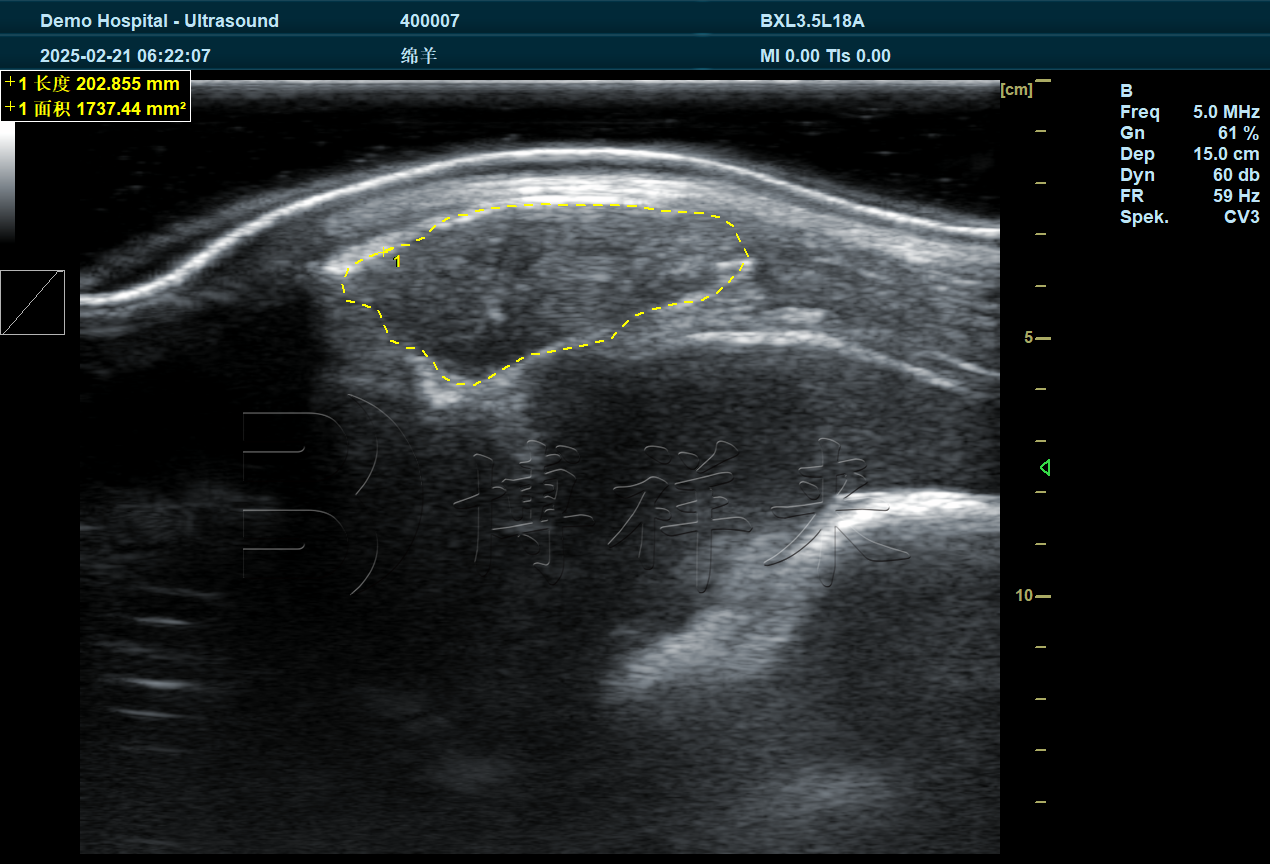

羊的毛发和表皮特点对检测效果有显著影响。像绵羊这种毛发较长的品种,一般不需要刮毛,只需拨开毛发并涂抹耦合剂,就能获得清晰影像。但对于毛发短小、细密的羊,往往需要剃毛,否则超声波难以透过,影响图像质量。

更值得注意的是,羊的皮肤对超声波的吸收非常强,这也是许多通用B超机在做羊背膘眼肌检测时,图像模糊、不够清晰的主要原因。因此,专门为羊设计的背膘眼肌测定仪必须具备更强的穿透力和成像优化功能。

3. 检测参数与图像需求

在羊场实际生产中,检测的核心指标主要包括:

背膘厚度:反映脂肪沉积情况,是肉质评估的重要依据;

眼肌宽度与面积:决定了瘦肉率和肉质等级,是羊育种和出栏评定的关键参数。

目前,市场上一些普通B超机仅能测量背膘厚度,而没有配备 眼肌宽度与面积测量的专门设置。这就导致数据不完整,难以满足育种和科研需求。而专业的羊用背膘眼肌测定仪,能够在图像上直接标注宽度和面积数据,大大提升了检测效率和科学性。